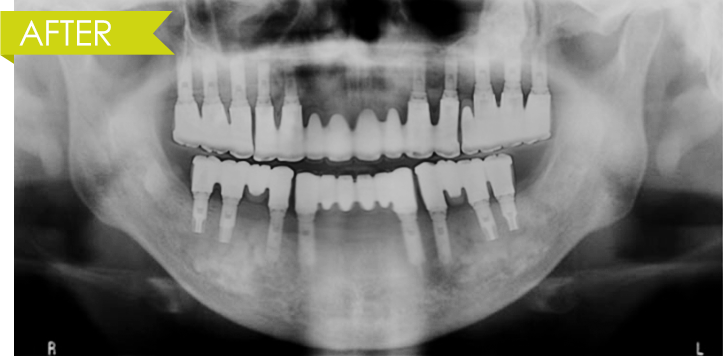

치아가 모두 상실된 경우, 16~20개 임플란트 식립

자연치아가 사고나 충치, 잇몸질환 등의 이유로 모두 상실된 경우 치아가 본래의 치아와 같은 역할을 할 수 있도록 임플란트를 16~20개 정도 식립해야 합니다.

임플란트 식립

임플란트가 들어갈 위치에 무치악 임플란트를 이식,

잇몸을 엎어 잇몸뼈간의 결합을 유도합니다.

보철물 삽입/관리

임플란트 위에 치아 보철물을 구강에

장착하여 치료를 마친 후 유지관리 합니다.